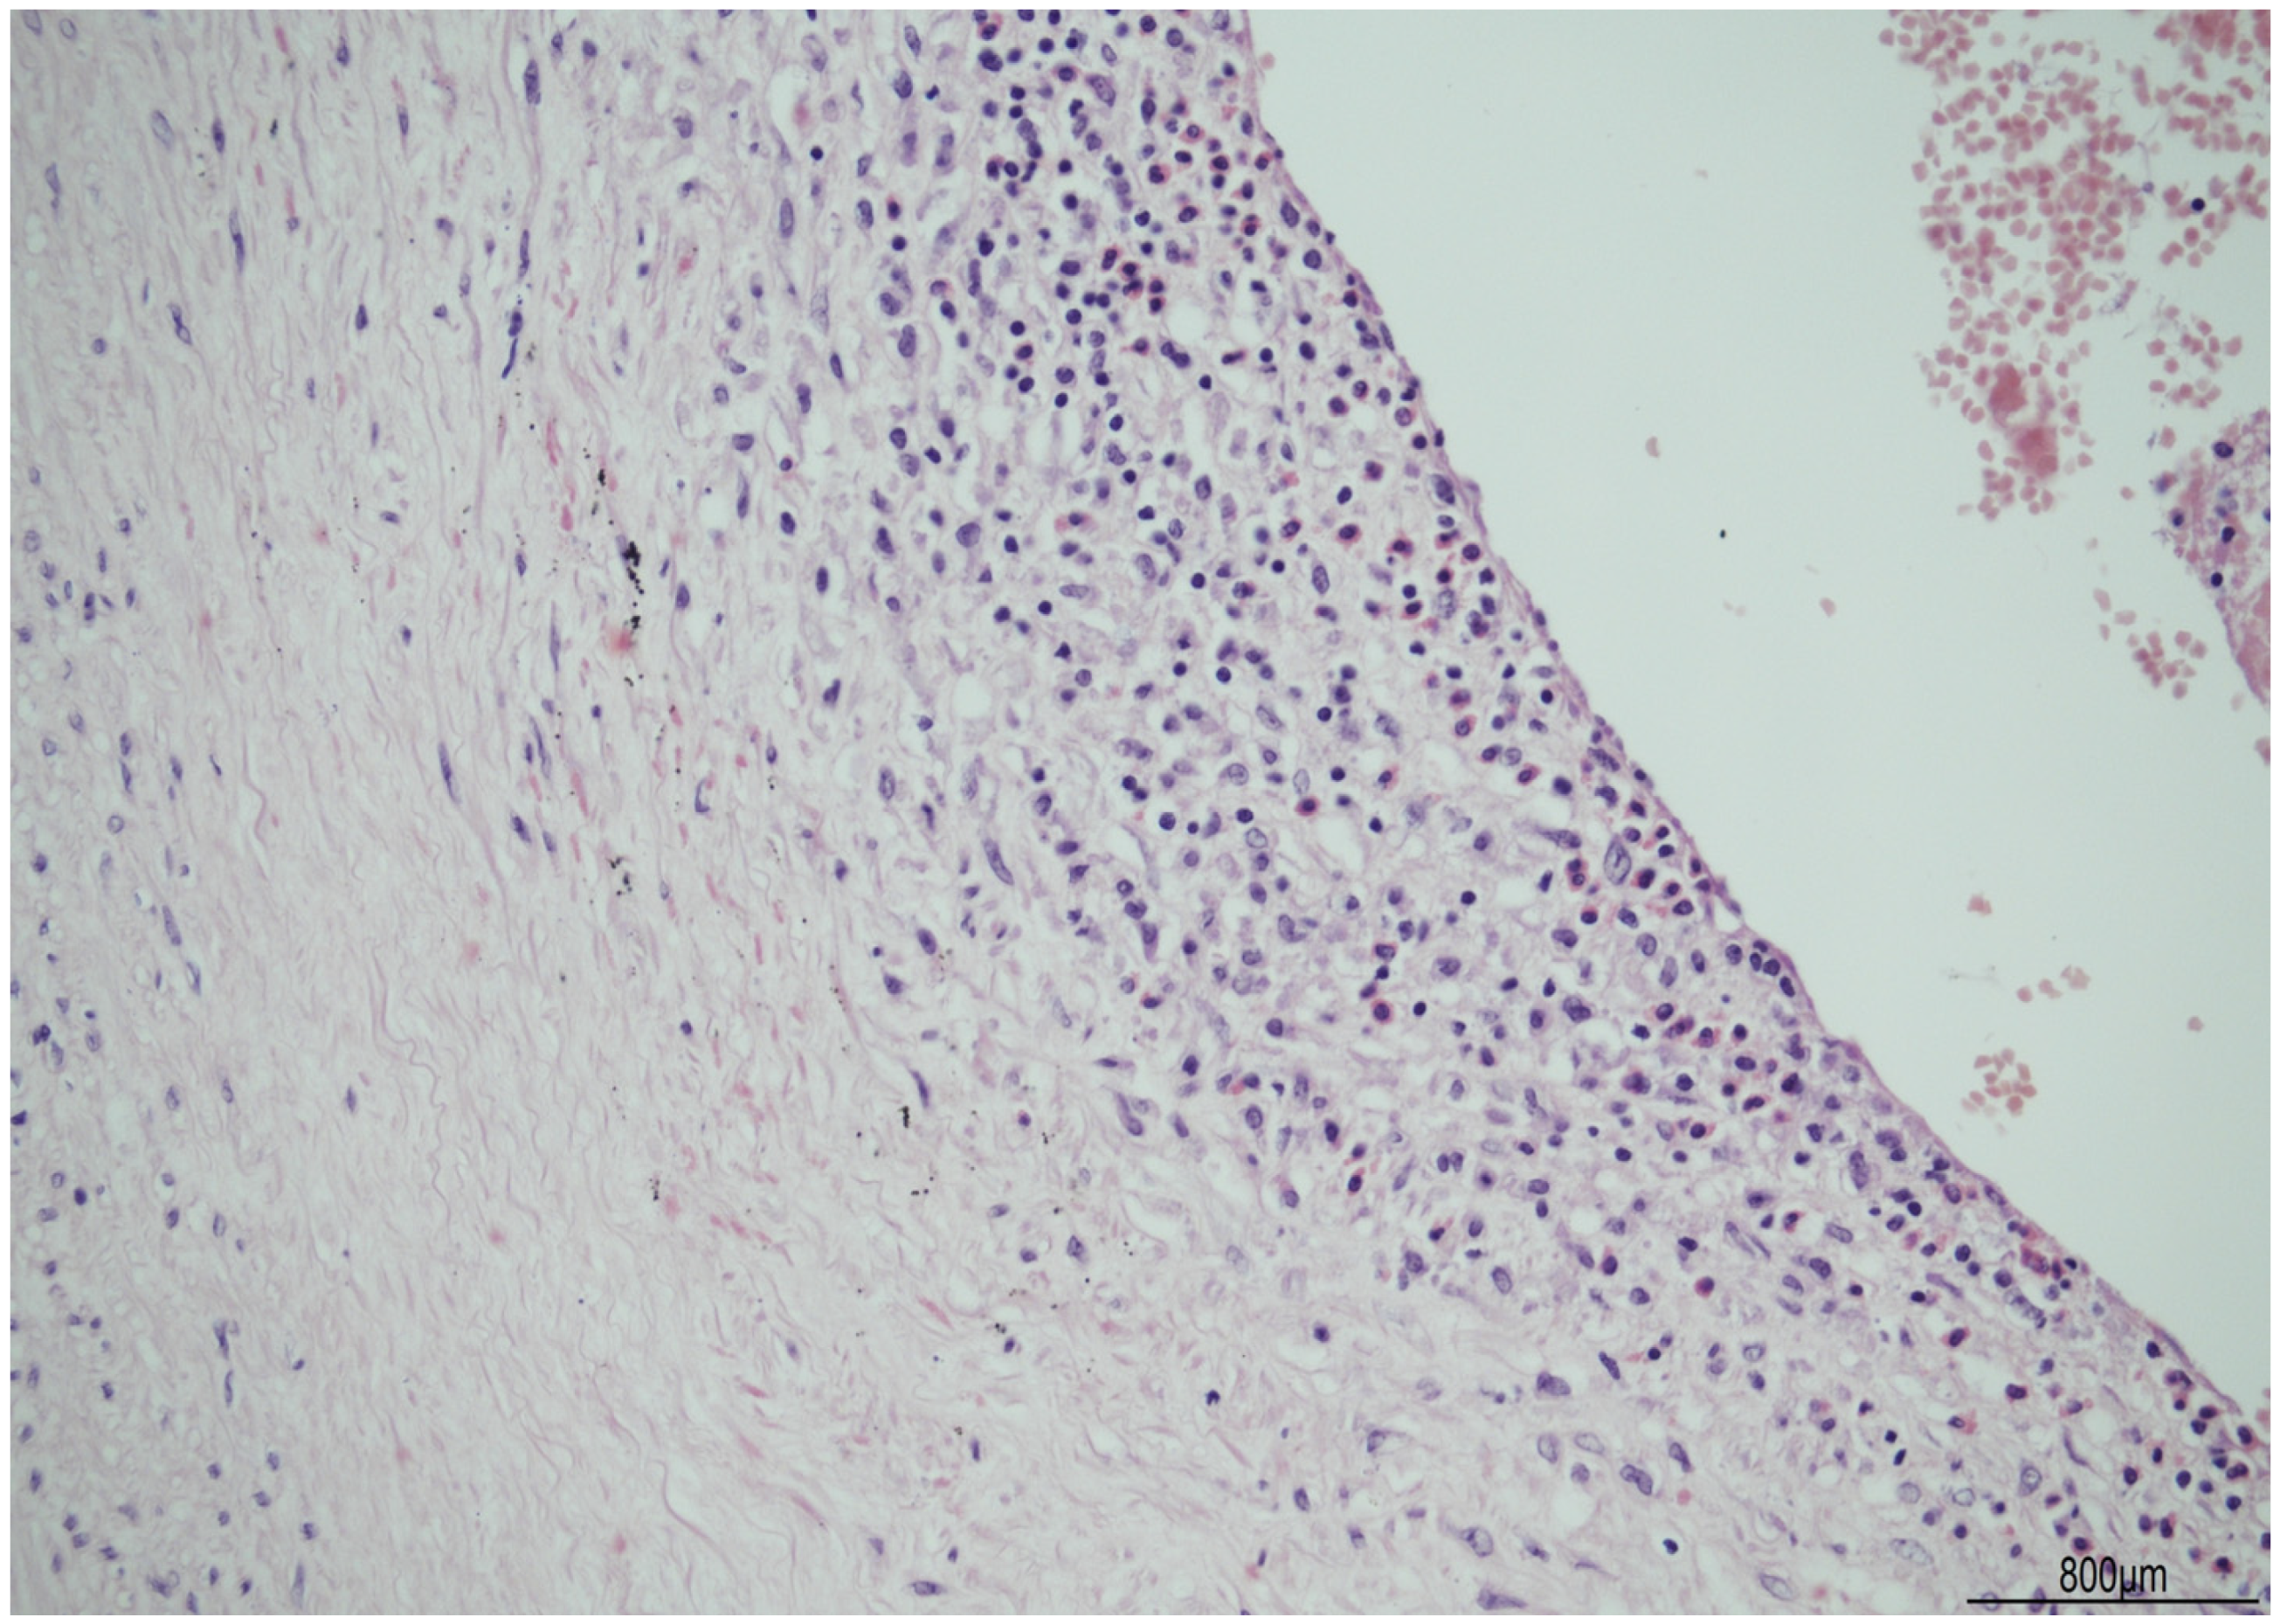

Discordant Eosinophilic/T-Cell Chorionic Vasculitis in a Dichorionic Diamniotic Placenta

Silvestri, E.; Servadei, F.; Tamagnini, I.; Moretti, L.; Bonasoni, M.P. Discordant Eosinophilic/T-Cell Chorionic Vasculitis in a Dichorionic Diamniotic Placenta. Int. J. Mol. Sci. 2023, 24, 9207. https://doi.org/10.3390/ijms24119207